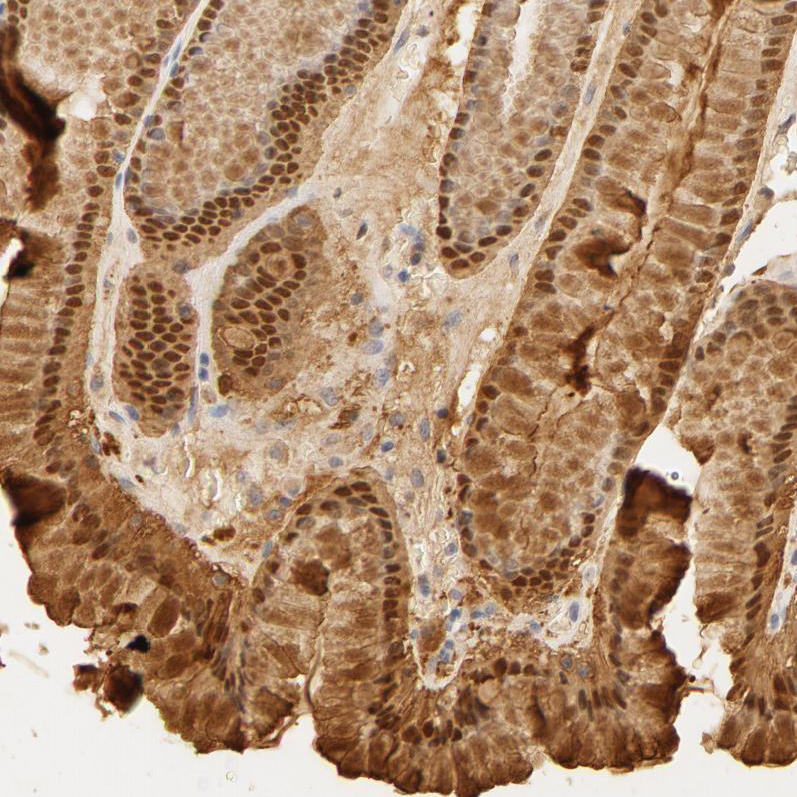

Immunohistochemical staining of human duodenum shows moderate cytoplasmic and nuclear positivity in glandular cells.